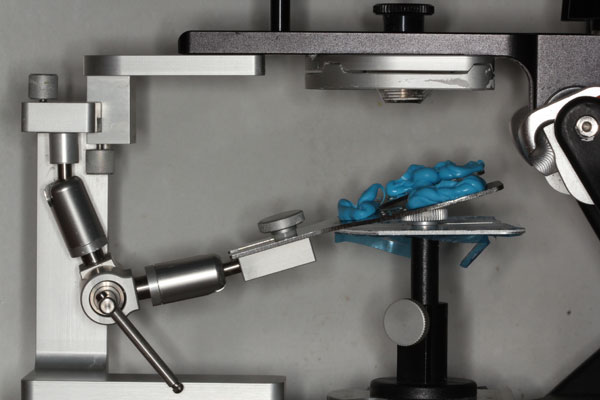

TREATMENT PROTOCOL: